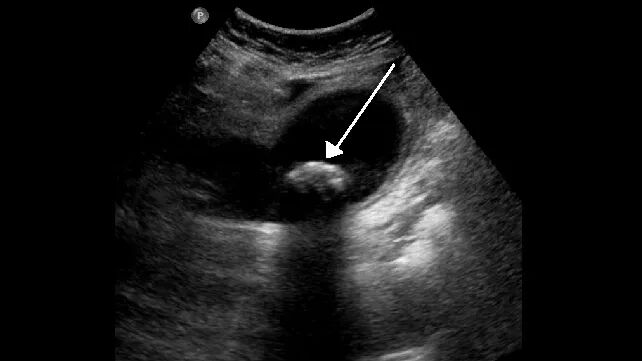

胆结石是坚硬的卵石状物质,在胆囊中形成,许多人其实没有明显症状,也可能不知道自己是否患有胆结石。

图源 healthline.com

当这些结石四处移动导致阻塞管道(连接胆囊和肠道的管状通道)时,才会出现恶心、呕吐或腹部、背部或右臂下方疼痛等症状,情况严重时候可能需要手术治疗。